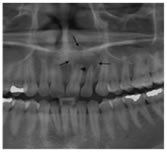

4

Figure 4: Dentigerous cyst (white arrows) related to an unerupted right mandibular third molar, shown on a panoramic MIP reconstruction from a CT of the mandible. Note the mild inferior displacement of the inferior alveolar canal (black arrowheads) by the cyst.